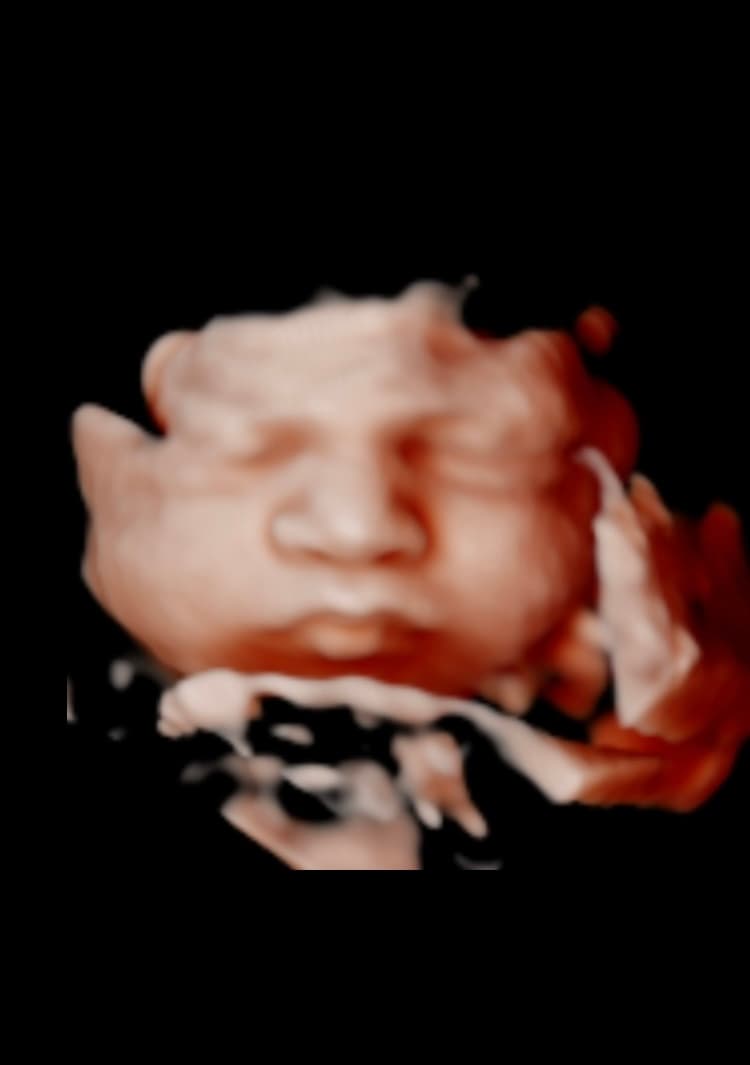

Explore our collection of ultrasound images and clinic photos. See the quality and clarity of our technology and the comfort of our facilities.

Book an appointment today and capture beautiful images of your baby. Our state-of-the-art technology provides clear, detailed ultrasound images for you to cherish forever.